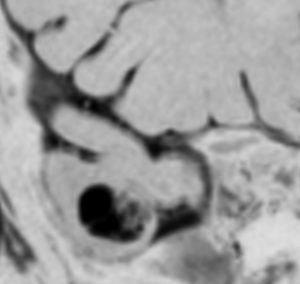

手術中の顔面筋電放電をモニターしたものです。過誤腫の摘出によって沈静化消失しています。

結果的に過誤腫をほぼ全摘出してしまったのですが,脳幹背側なので神経核損傷のリスクを伴います。亜全摘出でも発作は止まるとされています。手術中のモニターで放電が無くなればそこで過誤腫の摘出を中止して良いのでしょう。